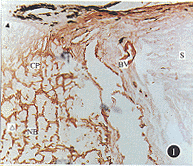

讨论  本研究用较为敏感的免疫过氧化酶ABC法,观察正常成人视乳头筛板细胞外基质。结果表明,正常成人视乳头筛板存在大量Ⅳ型胶原蛋白和层连接蛋白,这些大分子呈薄片形式横向排列于巩膜管中。巩膜中除血管外,无这两种大分子。筛板中除血管外,无纤维连接蛋白。这与Hernandez等[1,2]和Goldbaum等[3]报告的结果一致。

Ⅳ型胶原蛋白和层连接蛋白是所有基底膜结构的两种主要成分。本研究结果表明,筛板细胞外基质中含有基底膜样物质。组织学研究发现,在视乳头筛板前区、筛板和筛板后区的神经细胞和间质型胶原之间均有一层星形胶质细胞,这些胶质细胞对胶质纤维酸性蛋白抗体(GFAP)呈阳性反应,筛板中基底膜大分子可能由该细胞合成[4]。

在筛板,基底膜样物质呈线性膜包绕筛板并由筛板表面呈条纹状延伸到筛板中心。电镜观察证实包裹筛板的胶质细胞有突起延伸到筛板中,由Ⅳ型胶原蛋白和层连接蛋白构成的基底膜包绕这些胶质细胞[5]。这种结构可能加强了筛板对神经束的固定作用,在青光眼眼压升高过程中,筛板形态发生慢性改变,上述结构分布可能使固定在筛板上的神经束扭曲,成为视神经轴浆流受阻的原因。

在筛板后区,神经束膜的细胞外基质是筛板的延续。筛板和筛板后区细胞外基质的区别是筛板的细胞外基质成分浓度高,呈板状,方向与神经垂直。基于Ⅳ型胶原蛋白和层连接蛋白的吸附特点,这两种大分子可能将神经纤维连接到胶质束膜上,对穿过的视神经轴突具有机械支持作用,并可能在胚胎神经纤维生长过程中发挥引导作用[6,7]。

由本研究结果可见,筛板不是巩膜组织的一部分,其成分构成和分布均与巩膜不同。Hernandez等[1]认为筛板是中枢神经系统的一种特殊组织,对通过其中的视神经具有营养和支持作用。